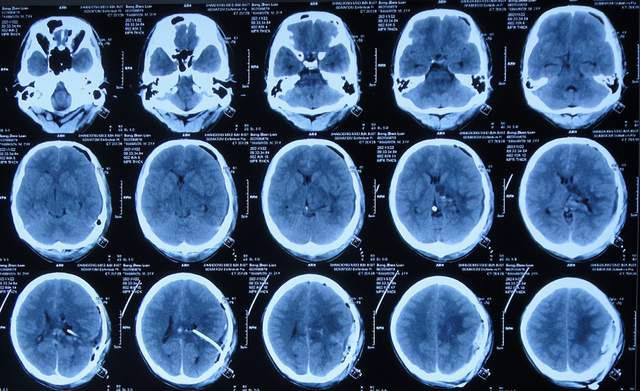

继续抗感染治疗1周的时间,仍精神差,食欲差,间断发热,期间3次查头颅影像(2021年1月29日头颅核磁增强(图-10)、2021年1月31日头颅CT(图-11)、2021年2月3日头颅核磁增强(图-12)均示颞角逐渐有扩张,有感染。

图-10:2021年1月29日头颅核磁增强

图-11:2021年1月31日头颅CT

图-12:2021年2月3日头颅核磁增强

脑膜瘤术后3周,间断发热2周,因治疗不见好转,且颞角稍有扩张,因此为了更专业的治疗,拔除腰大池引流管后转至北京北亚骨科医院的李小勇脑脊液科。

2021年2月5日(脑膜瘤切除术后颅内感染3周)住入李小勇脑脊液科,入院时:精神差,食欲差,体温高(图-13);查头颅CT示脑瘤术后状态(图-14);(外院)2021年2月3日头颅核磁示有脑脓肿(图-12)。

图-13:2021年2月5日入院时

图-14:2021年2月5日头颅CT

入院后3天即2021年2月8日,左颞角脑室腹壁外引流术(图-15)。

图-15:2021年2月8日头颅CT

左颞角脑室腹壁外引流术后8天即2021年2月16日,查头颅CT示颞角缩小(图-16)。

图-16:2021年2月16日头颅CT

左颞角脑室腹壁外引流术后21天即2021年3月1日,查头颅CT示颞角仍有扩张(图-17)。

图-17:2021年3月1日头颅CT

左颞角脑室腹壁外引流术后23天即2021年3月3日,头颅CT增强和核磁增强示有脑脓肿(图-18、图-19)。

图-18:2021年3月3日头颅CT增强

图-19:2021年3月3日头颅核磁增强

2021年3月8日(左颞角脑室腹壁外引流术后28天),进行了脑脓肿切除术(图-20)。

图-20:2021年3月8日头颅CT

2021年3月9日(左颞角脑室腹壁外引流术后29天,脑脓肿切除术后次日),查头颅CT示脑脓肿切除术后(图-21)。

图-21:2021年3月9日头颅CT